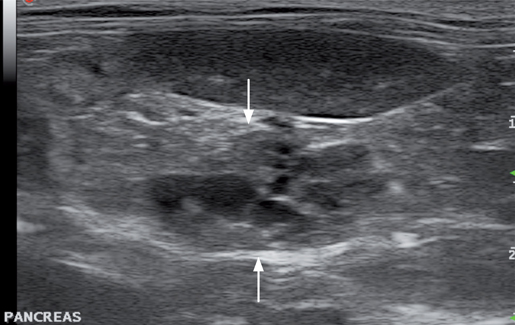

假性囊肿是胰腺炎的后遗症之一。假性囊肿是圆形的病灶,在纤维性包囊内充满含有胰酶和细胞碎屑的液体。多见于胰腺左叶。假性囊肿的囊壁较厚,内容物呈无回声或低回声并伴有后方回声增强。

先天性胰腺囊肿的大小差异很大,通常与多囊肾及多囊肝有关。囊肿的壁由一层单层上皮细胞构成。潴留性胰腺囊肿是由胰管阻塞或分泌物蓄积产生的。潴留性胰腺囊肿一般很小,也没有临床症状。两种类型的囊肿的内容物都是无回声的,囊壁很薄或不可见,并伴有后方回声增强(图. 15)。